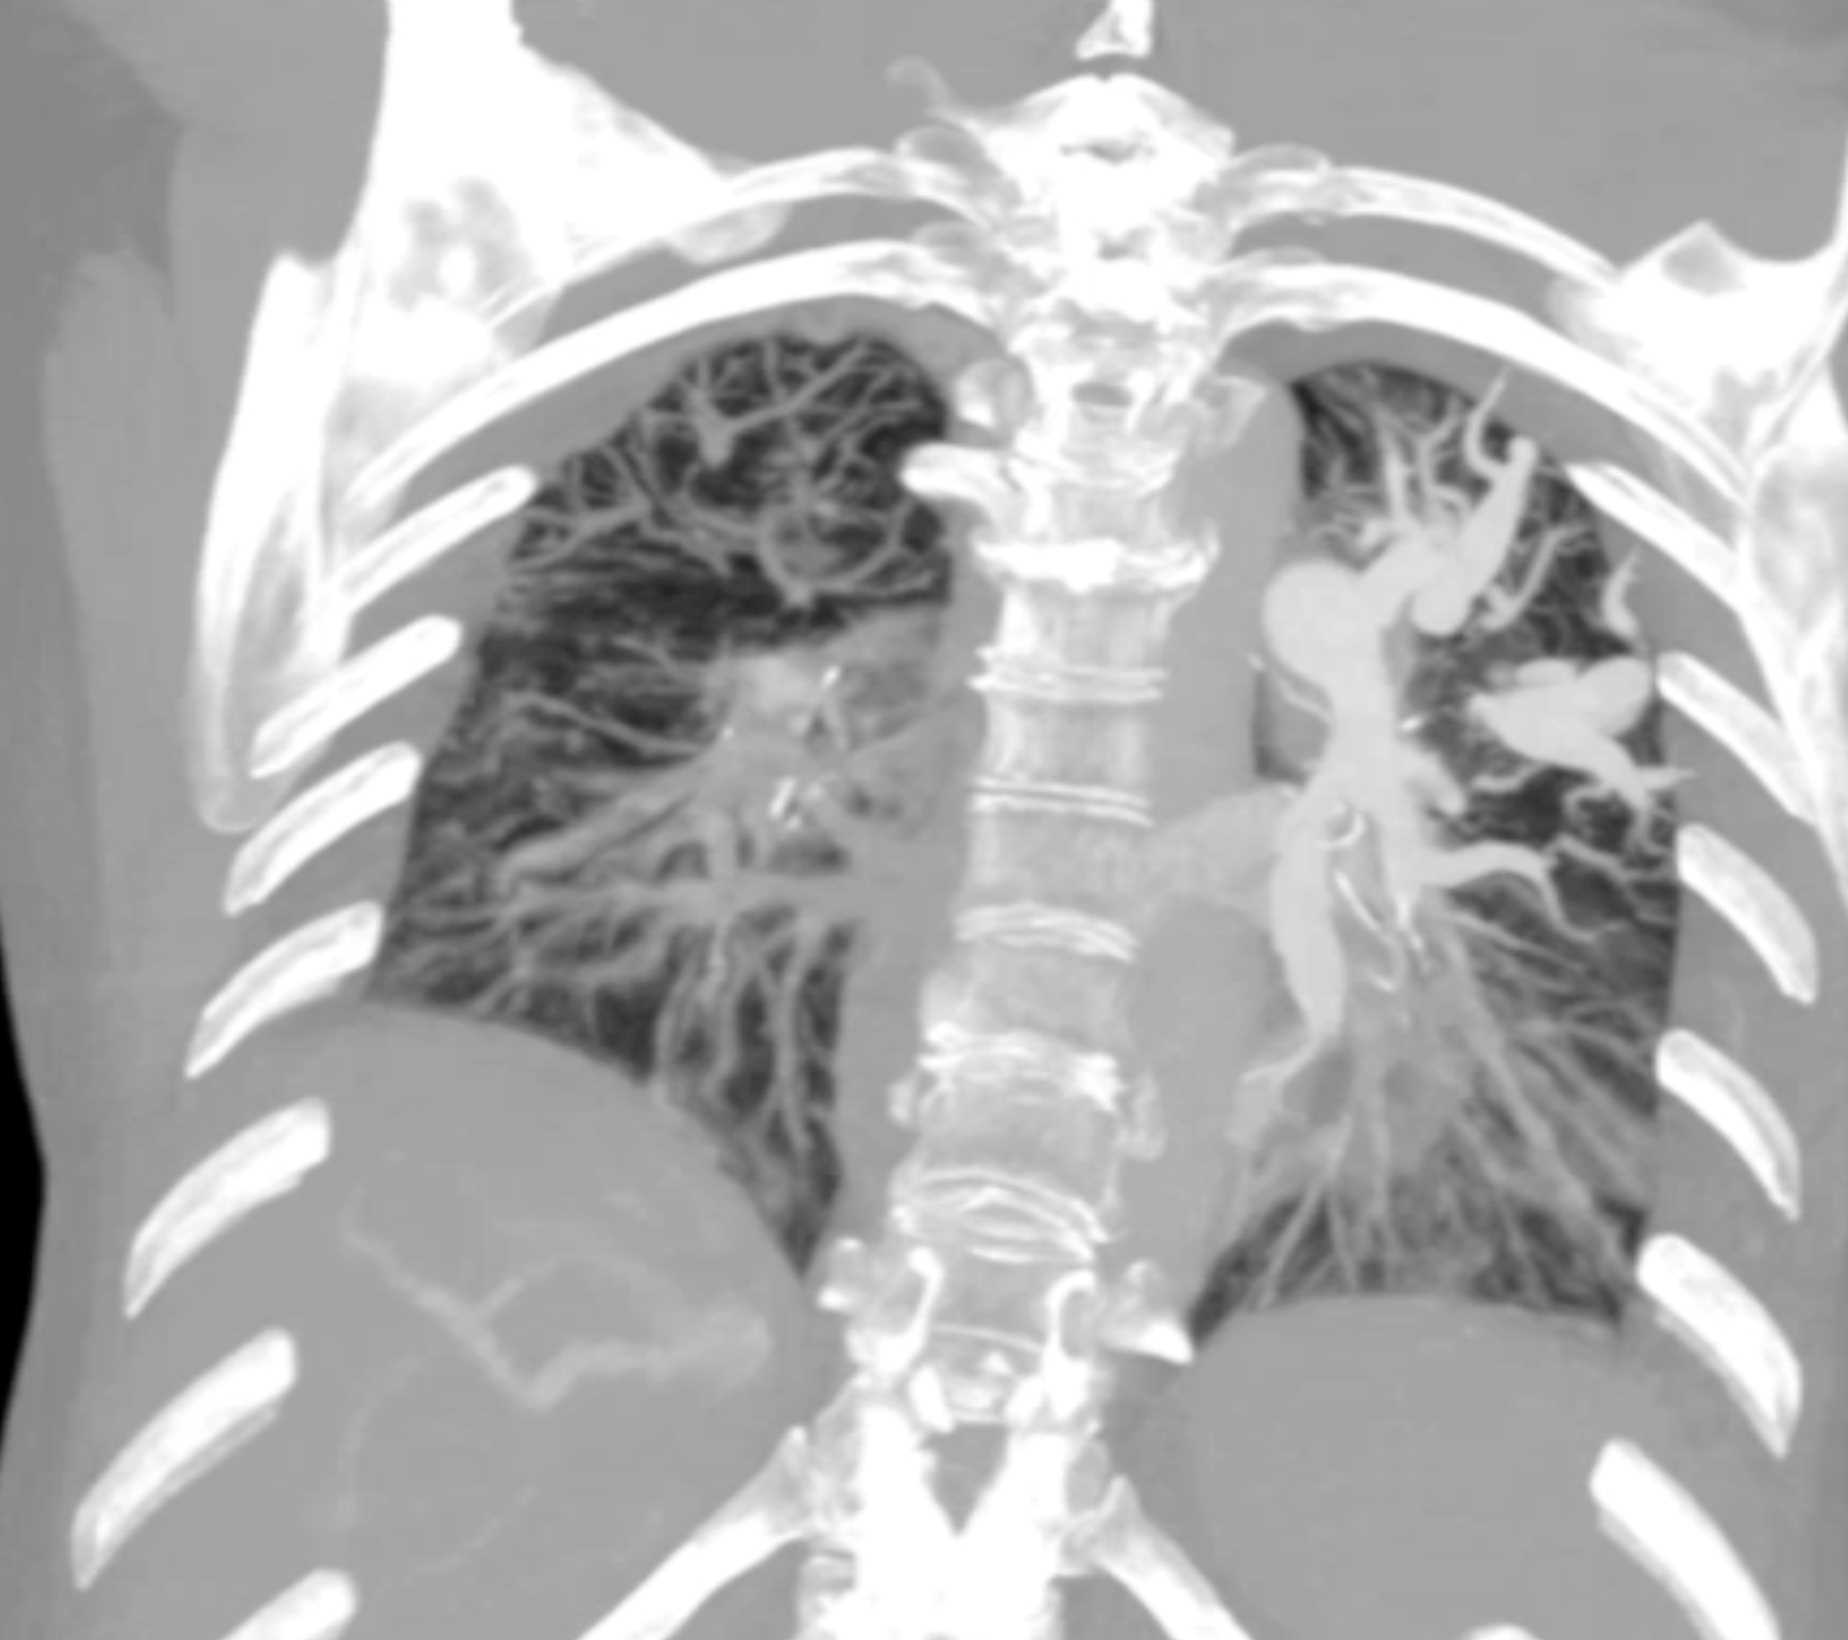

Fibrosing Mediastinitis involves the Pulmonary Artery and Vein